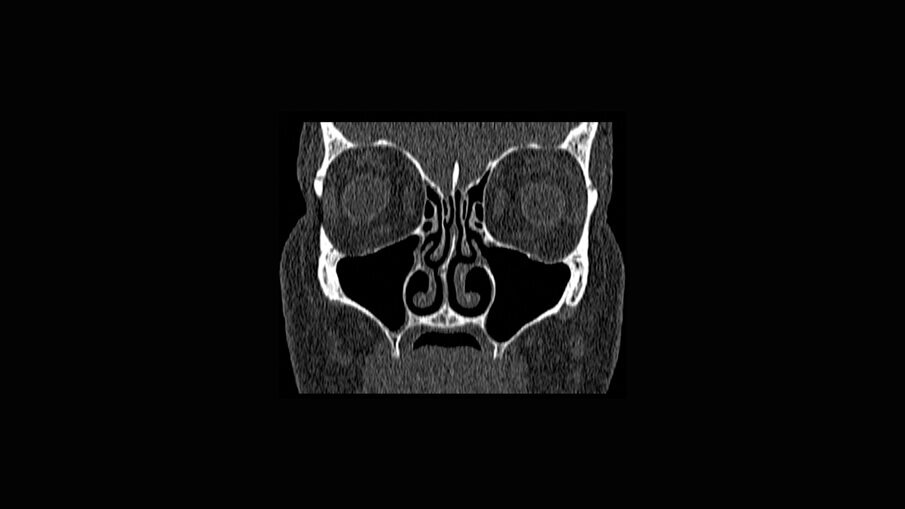

- pianificazione chirurgica della riabilitazione con valutazioni anatomiche, TC Cone-Beam, stereolitografia (SLA), funzionale al progetto protesico;

È presentata una riabilitazione con 4 impianti zigomatici (QUAD) in paziente con grave atrofia del mascellare. In questo caso la protesi con carico funzionale è stata consegnata alla paziente dopo 72 ore. Nelle immagini 1-4 viene mostrata la stereolitografia e la TC della paziente, mentre nelle immagini 5-7 viene mostrata la situazione iniziale e finale della paziente.